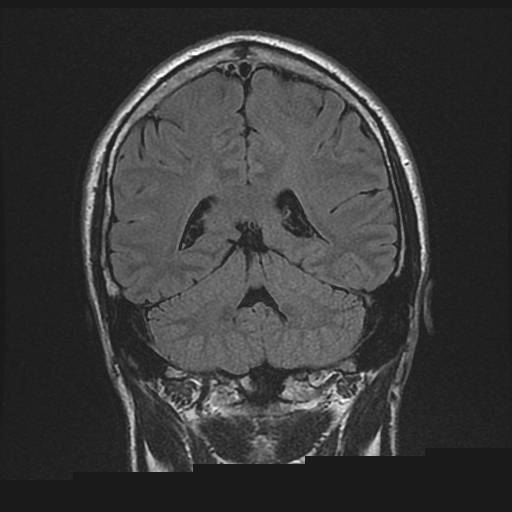

Billede 4: Normal hjerne, coronalt snit (set bagfra) hos en anden patient end billede nr. 2.

MR-billederne viser fire forskellige optagelser af en normal hjerne. Cerebrospinalvæsken er hvid på billede 1 og 3, mens den er sort på 2 og 4. Man ser tydeligt forskellen på grå og hvid substans i hjernen, det ses bedst på 2 og 4.